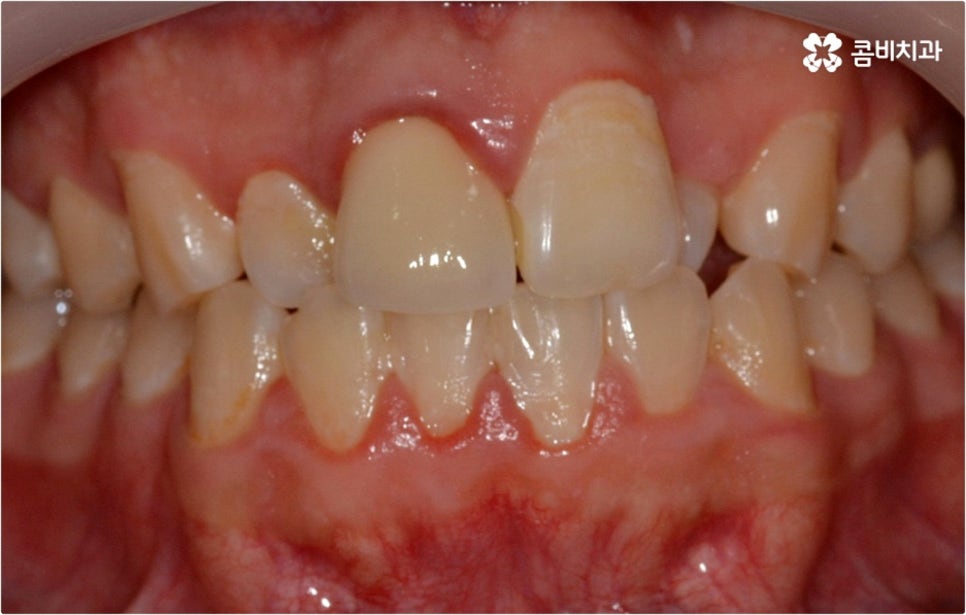

웃을 때 살짝 드러나는 덧니는 사람에 따라 매력 포인트로 느껴지는 경우도 있지만 구강 건강 측면에서 보면 치아와 치아가 겹쳐진 부분에 음식물 찌꺼기가 남아 치석이 쌓이기 쉽기 때문에 충치나 잇몸병이 더 자주 발생할 수 있으므로 주의하실 필요가 있습니다. 이와 같이 덧니는 옆 치아와 잇몸에까지 지속적으로 좋지...

출처 아카이브 열기웃을 때 살짝 드러나는 덧니는 사람에 따라 매력 포인트로 느껴지는 경우도 있지만 구강 건강 측면에서 보면 치아와 치아가 겹쳐진 부분에 음식물 찌꺼기가 남아 치석이 쌓이기 쉽기 때문에 충치나 잇몸병이 더 자주 발생할 수 있으므로 주의하실 필요가 있습니다. 이와 같이 덧니는 옆 치아와 잇몸에까지 지속적으로 좋지 않은 영향을 주기 때문에 개선해 주는 게 좋은데요, 특히 덧니의 개수가 많아 삐뚤빼뚤한 정도가 심하다면 교합이 잘 맞지 않아 씹기가 불편하거나 턱관절 압박, 통증 등을 유발할 수 있으며 나아가 안면비대칭으로 이어질 수 있기 때문에 방치하지 말고 될 수 있는대로 빨리 덧니교정 을 통해 이를 바로잡아 주시길 권유드리고 있습니다.

요즘은 관련 치의학 기술이 많이 발달하고 장치도 다양해져서 교정 치료가 예전보다는 훨씬 더 대중화 되었다고 볼 수 있으나 그럼에도 불구하고 막상 덧니교정 을 시작하려고 하면 오래 걸리는 시간이나 치아 이동 통증, 비용적인 부담 등의 이유로 망설여지는 분들도 있을 거예요. 또한 덧니교정 의 적기가 따로 있는지, 덧니를 교정할때 반드시 치아를 발치하는지에 대해서도 자주 문의를 주시고 있는데요.

덧니교정 시 환자분들의 상황에 따라 치아 이동에 필요한 공간이 부족하지 않다면 비발치 교정이 가능한데요, 이런 경우 치아 사이를 살짝 갈아서 여유 공간을 만드는 치간 삭제 방법, 마지막 어금니를 후방으로 이동시키는 방법, 그리고 악궁 확장 장치를 사용해 치아 사이를 벌려주는 방법 등 다양한 방법으로 공간을 만들어 치열을 가지런하게 바로잡아 줄 수 있습니다. 이때 환자분들의 구강 상태, 즉 악궁 크기 대비 치아의 크기, 치아가 겹친 정도, 덧니의 위치와 개수 등을 자세하게 검진한 다음 치아가 이동할 충분한 공간이 확보되지 않는다면 발치 교정을 하게 될 거예요.